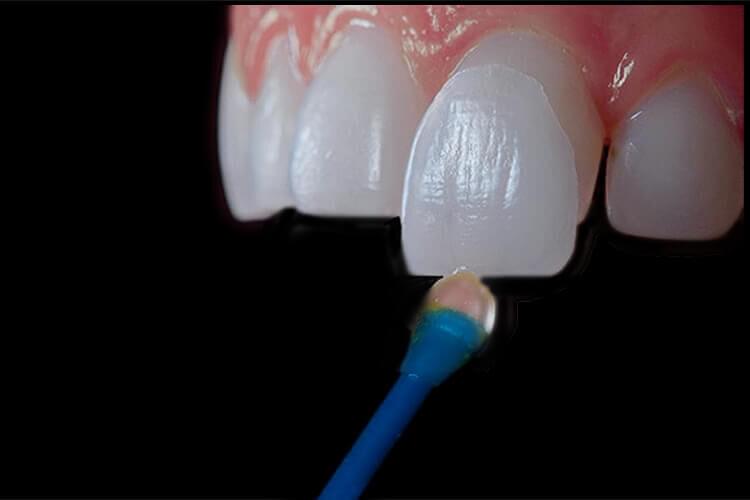

- Вініри - тонкі пластинки, які надають зубам ідеальну форму та кольорову гаму, приховуючи недоліки.

Вініри:

Красива білосніжна посмішка - мрія багатьох людей, тому відбілювання зубів і ортодонтія так популярні. На жаль, хвороби та інші фактори можуть назавжди змінити колір емалі, а форма наших зубів може бути далека від ідеальної навіть після видалення ортодонтичного пристосування. У таких випадках вініри - гарне рішення, оскільки вони усувають естетичні недоліки зубів і надають зубам здоровий і, перш за все, природний вигляд. У статті ми розповімо, що таке вініри і які їхні можливості

Вініри - тонкі пластинки з кераміки або композитних матеріалів, які накладаються на передню частину зубів, забезпечуючи ідеальну форму та колір.

Вініри надають природний вигляд, не вимагають великого знесіння зубів та швидко та ефективно виправляють косметичні дефекти.